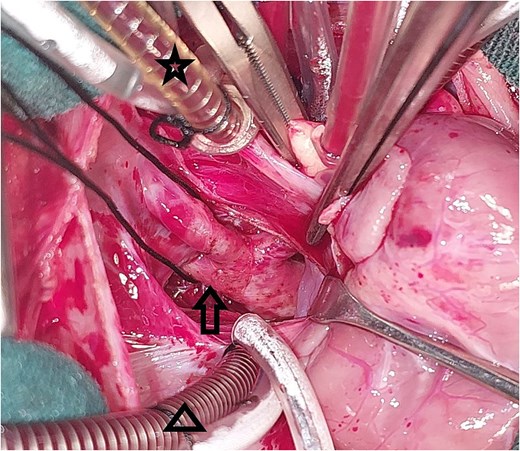

A 20-day-old boy with an unremarkable perinatal history was referred to the pediatric emergency department with respiratory distress. The physical examination revealed poor general condition and central cyanosis. The pulses were bounding in both brachial arteries but the femoral arteries were not palpable. A systolic murmur grade 4/6 was heard along the left sternal edge. The liver was enlarged 2 cm below the costal margin. Transthoracic echocardiography (TTE) was performed and revealed infracardiac TAPVC with associated CoA. Computed tomography angiography (CTA) confirmed the diagnosis of CoA (Fig. 1), and for technical issues, the pathway of CPC was not apparent on CTA. TTE was repeated and the drainage of the CPC into the portal vein was confirmed. The heart team at our hospital decided for urgent surgical repair. At first, the repair of CoA was performed through left thoracotomy with patch plasty technique since the stenosis was too long, and it was not possible to perform resection and end-to-end anastomosis. Then, through median sternotomy, the pericardium was opened, and a total cardiopulmonary bypass (CPB) was prepared. The heart was arrested with an antegrade cold blood cardioplegic solution. The CPC was seen behind the pericardium (Fig. 2). The VV was descending crossing the diaphragm, and it was dissected and controlled (Fig. 3). The heart was lifted out of the pericardium and a long incision was made in LA, and a parallel incision was made in the CPC (Fig. 4). A wide anastomosis was performed between these two incisions thus connecting the CPC into LA. The VV was permanently closed. RA was opened, and a small ASD was closed. The remainder of the operation was completed uneventfully. The patient was weaned off the CPB with stable hemodynamic conditions on low-dose inotropes (milrinone, epinephrin). Postoperative TTE showed normal pulmonary venous drainage without any gradient across the anastomosis, and excellent repair of CoA. After 48 hours on mechanical ventilation, the patient was extubated, and discharged from the ICU after 5 days. On one year follow-up, the patient was with normal growth, and in very good general condition without any complaints. TTE during the follow-up period revealed normal flow in the pulmonary veins.

Intraoperative image showing the opened left atrium (the arrow), and the opened pulmonary confluence (the star).